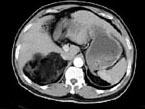

问题 男,59岁,右侧腰背酸痛,CT检查如图所示,应诊断为 ( )

选项 A、右腹膜后脂肪瘤 B、右肾血管平滑肌脂肪瘤 C、右肾上腺转移瘤 D、右肾上腺髓样脂肪瘤 E、右肾上腺腺瘤

答案 D